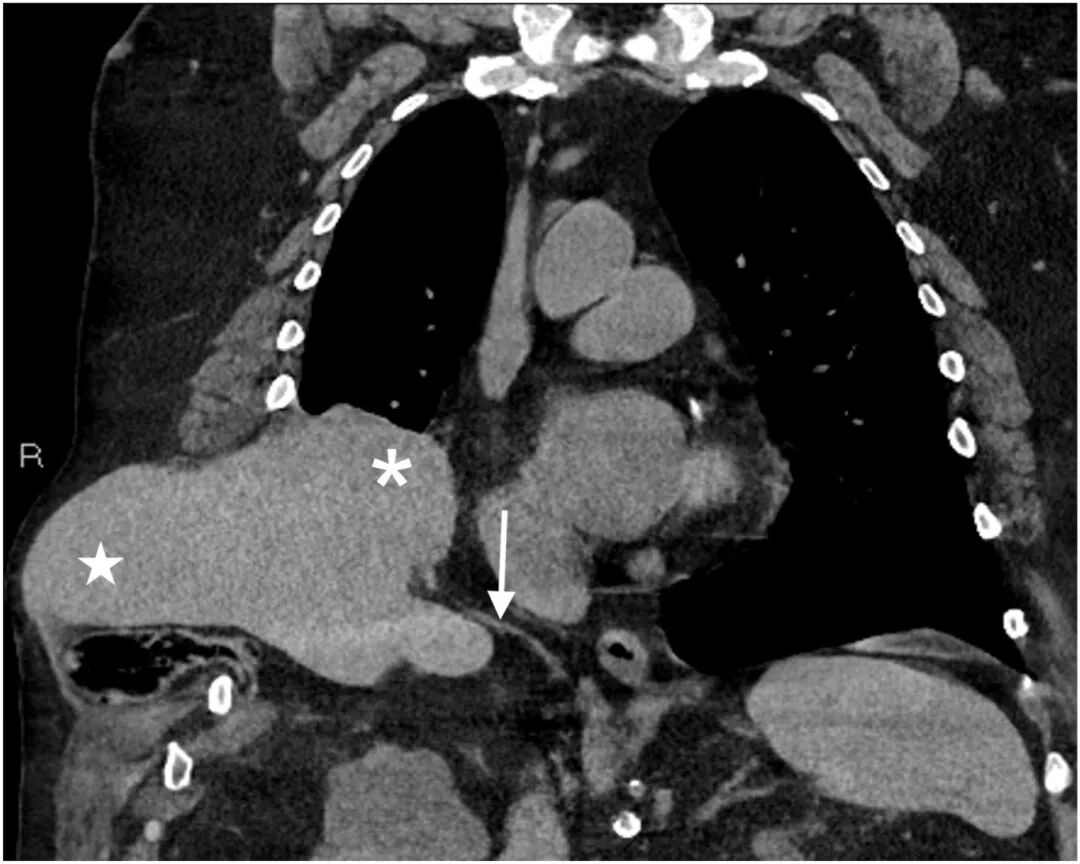

生命体征:血压126/91 mmHg,心率104次/分钟,未吸氧状态下血氧饱和度为 98%。体格检查发现,右上腹有一处无压痛、不可复位且可触及的隆起。行计算机断层扫描,如图1和图2所示。

图1:胸部对比增强计算机断层扫描(冠状位)显示肝脏(星号标示)经胸壁和膈肌疝入胸膜腔(*号标示)。右侧半膈用白色箭头标出。

诊断:腹壁肝疝。